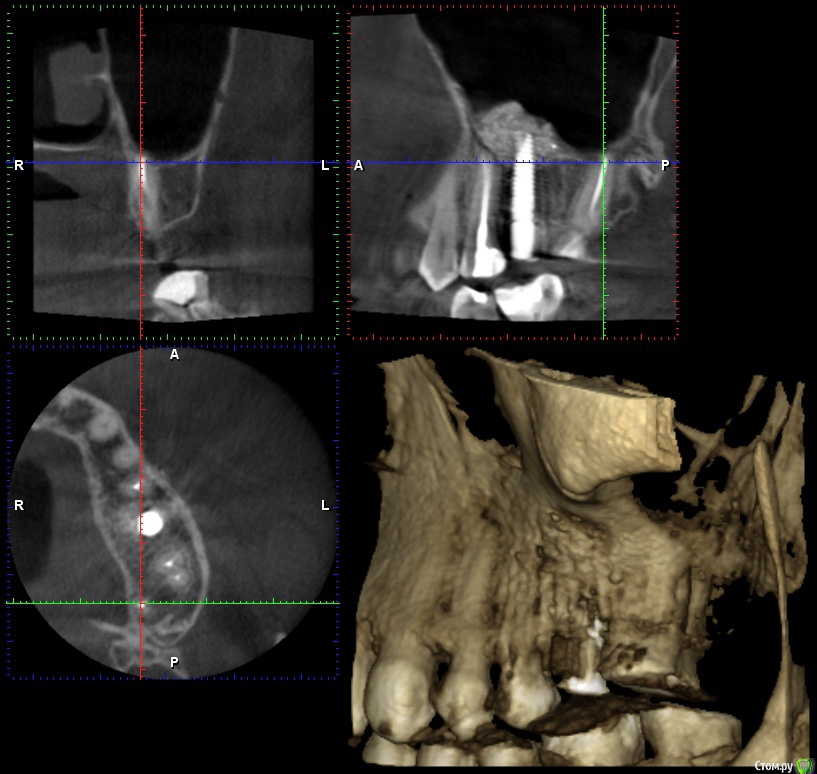

wladdX Опубликовано 26 января, 2017 Поделиться Опубликовано 26 января, 2017 Несколько скринов 2-й сегмент. Ссылка на комментарий

wladdX Опубликовано 26 января, 2017 Поделиться Опубликовано 26 января, 2017 (изменено) 3-й сегмент. Изменено 26 января, 2017 пользователем wladdX Ссылка на комментарий